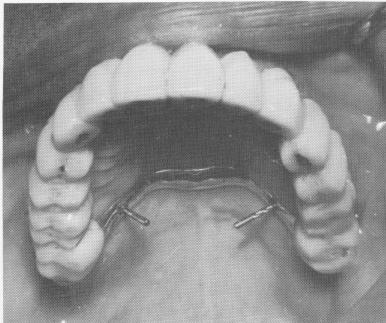

Fig. 4-38. Both posterior quadrants were easily removed, and the pin implants were still locked to the prosthesis.

3 Posterior quadrants removed, tripod pin implants locked to prosthesis